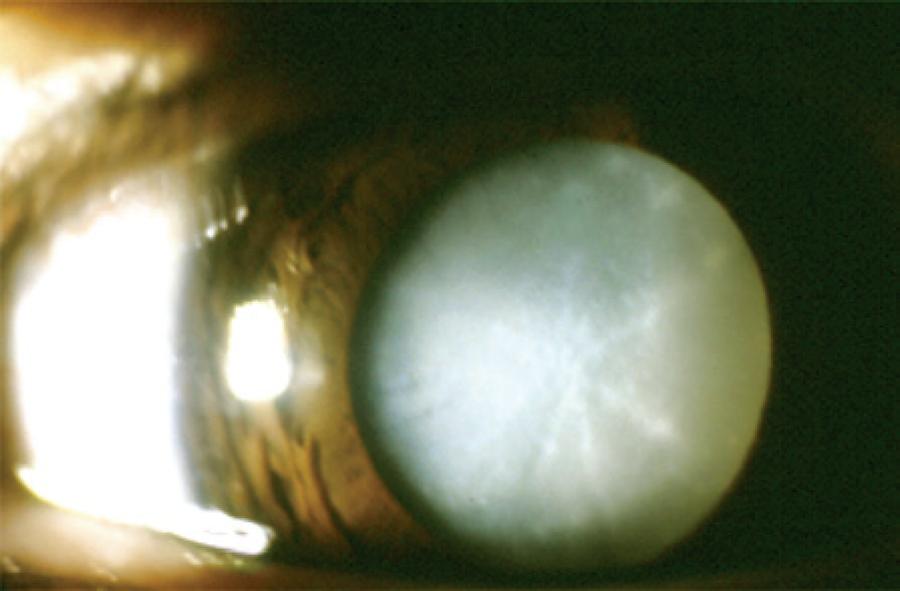

Cataract was classified according to the morphology as total (Figure 1), zonular, polar, capsular, and membranous. Zonular cataracts, which effect the fetal nucleus of the lens, were further classified as lamellar (Figure 2), pulverulent (Figure 3), nuclear (Figure 4), and sutural. According to the site of lens opacity, polar cataracts were classified as anterior, posterior, or pyramidal (Figure 5). Capsular cataracts were further classified as anterior, posterior, and lenticonus. When multiple morphological types of cataract co-exist in the same child or in the same eye, they are considered as mixed cataract.

Pediatric cataracts exhibit substantial heterogeneity. The opacity of the lens may affect the lens nucleus or alternatively the nucleus could remain transparent while the cortex or the lamellae surrounding the nucleus become opaque. The morphological diversity makes the morphological classification a challenging task. Additionally, there exists the possibility for overlapping morphologies. We found that zonular cataracts occurred with the highest frequency, in 72 (33.8%) patients. Among these cases, the lamellar subtype (Figure 2) was the most common (66.7%). Total cataract occurred in 66 (31.9%) patients (Figure 1).